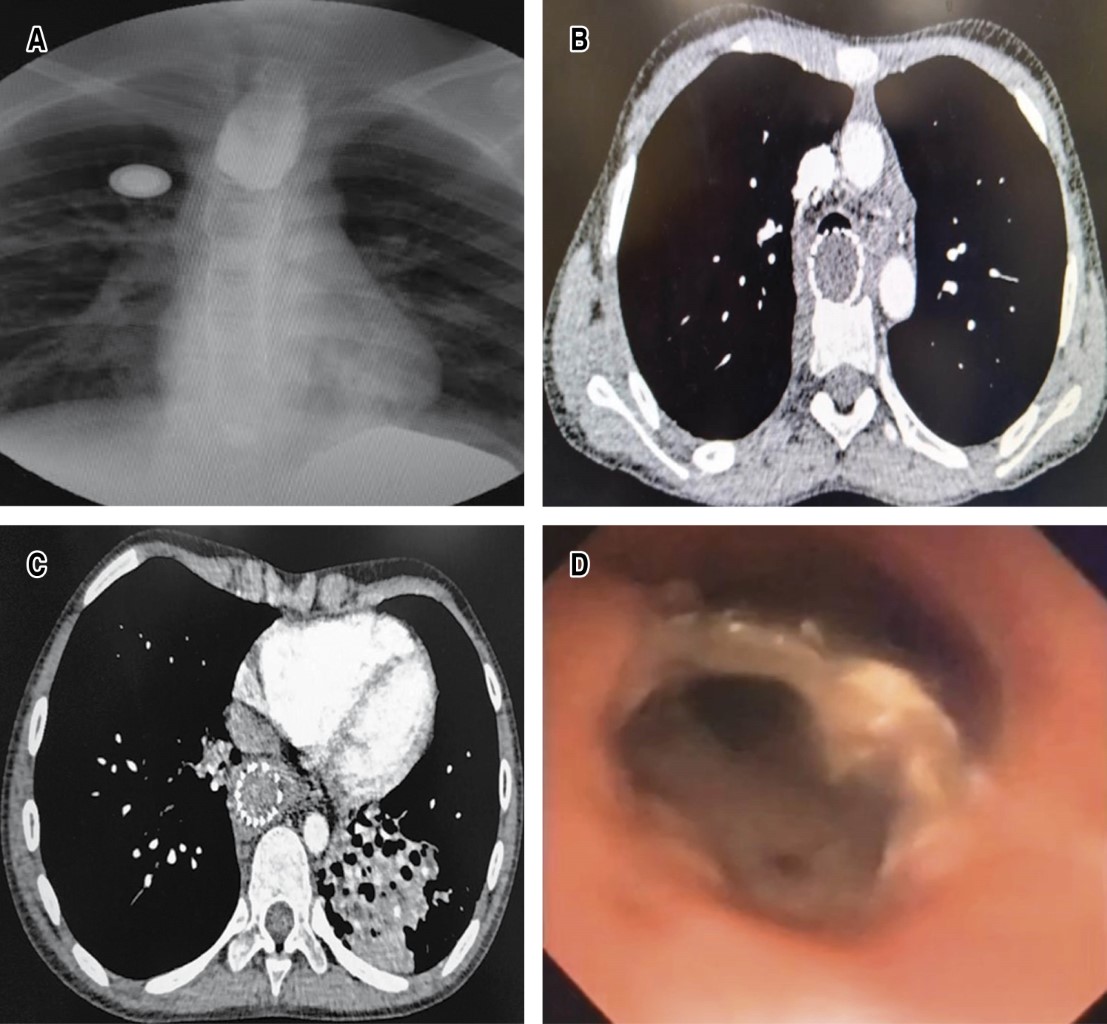

Radiology shows bronchial pattern and presence of intrathoracic radio-opaque esophageal prosthesis, esophagogram shows termination in blind end of the proximal esophagus, gastrogram shows distal esophagus with total stenosis and the distance between both ends of approximately 17 cm; digestive endoscopy shows total esophageal stenosis of the upper third, and the lower esophagus by gastrostomy view with critical and fibrous stenosis > 90% with total esophageal exclusion. The CT scan showed irreversible atelectasis of the left lower lobe due to bronchiectasis; bronchoscopy showed abundant bronchopulmonary suppuration originating in the left bronchus and a foreign body (metallic stent) was observed in the posterior wall of the proximal and middle third of the trachea with radical destruction of the membranous trachea adjacent to the stent, so a diagnosis of TAEF was made. Clinical and nutritional conditions improved with mixed parenteral nutrition and by gastrostomy bronchoscopic drainage of purulent secretions was performed weekly on three occasions and antibiotics were administered (Figure 1A-1D).